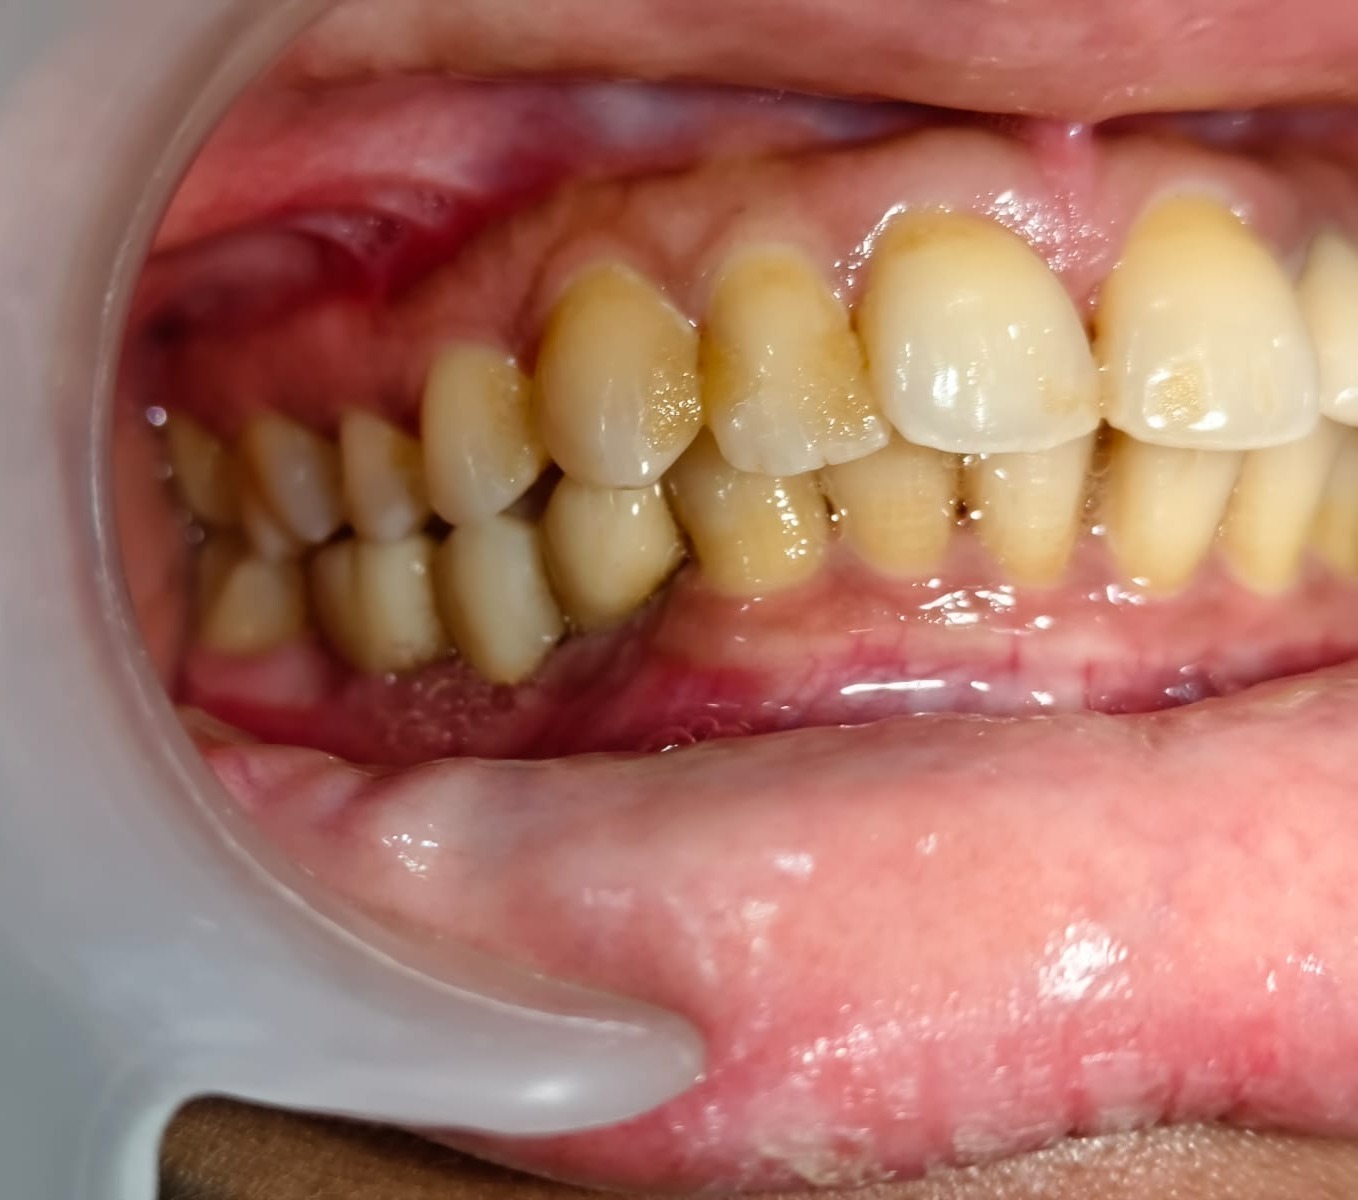

Healthy gums are essential for a healthy smile. However, many people in Mumbai experience gum problems such as bleeding gums, swelling, bad breath, or gum recession. Patients searching for affordable gum treatment in Mulund West Mumbai often want solutions that are effective, long-lasting, and within budget.

Gum disease (also called periodontal disease) usually begins with plaque buildup around the gums. If untreated, it can lead to infection, bone loss, and even tooth loss. The good news is that modern dentistry offers several treatment options depending on the severity of the condition.

Signs That You May Need Gum Treatment

You should consult a dentist if you notice:

• Bleeding while brushing

• Swollen or red gums

• Persistent bad breath

• Receding gums

• Loose teeth

• Pus around the gums